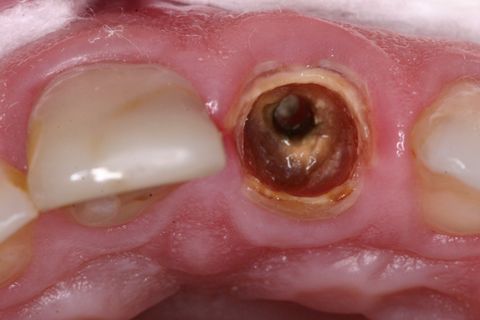

Aspecto Clínico Inicial

Paciente jovem do gênero masculino, apresentou-se à Clínica Integrada do Curso de Odontologia da Universidade Severino Sombra necessitando de um tratamento restaurador no dente 21. Ao exame clínico e radiográfico foi observado uma grande destruição coronária e tratamento endodontico satisfatório (Figuras 1, 2 e 3).

Foi proposto ao paciente a confecção de um pino anatômico afim de recuperar a função e a estética do dente e proporcionar a reabilitação futura do dente com uma coroa total em cerâmica.